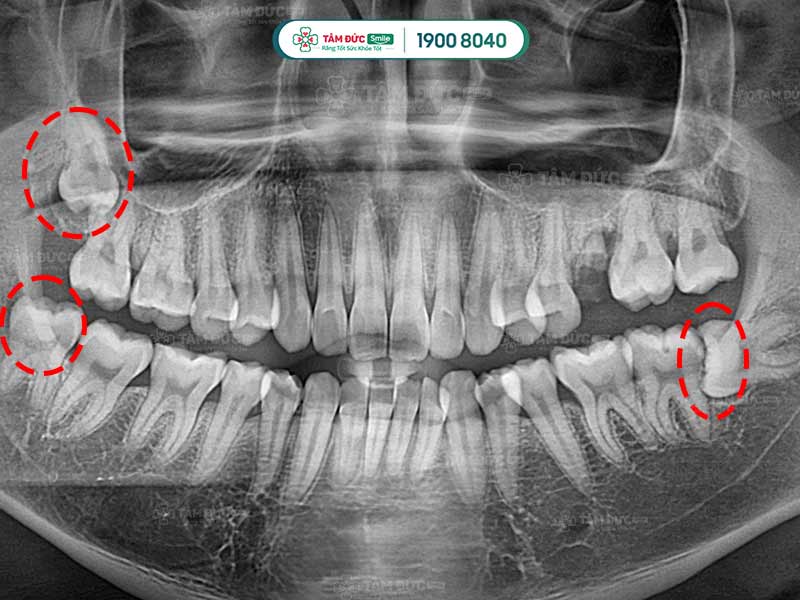

Quý khách có thể nhận biết răng khôn mọc ngầm thông qua phim chụp X-Quang

- Răng khôn mọc ngầm bị lệch, ảnh hưởng đến răng lân cận (răng số 7).

Trước khi nhổ bỏ răng khôn mọc ngầm, Quý khách được bác sĩ chụp X-quang răng và thực hiện các xét nghiệm máu cần thiết. Qua phim X-Quang, bác sĩ biết được ảnh hưởng của răng đang mọc ngầm để cân nhắc phương pháp điều trị thích hợp nhất.